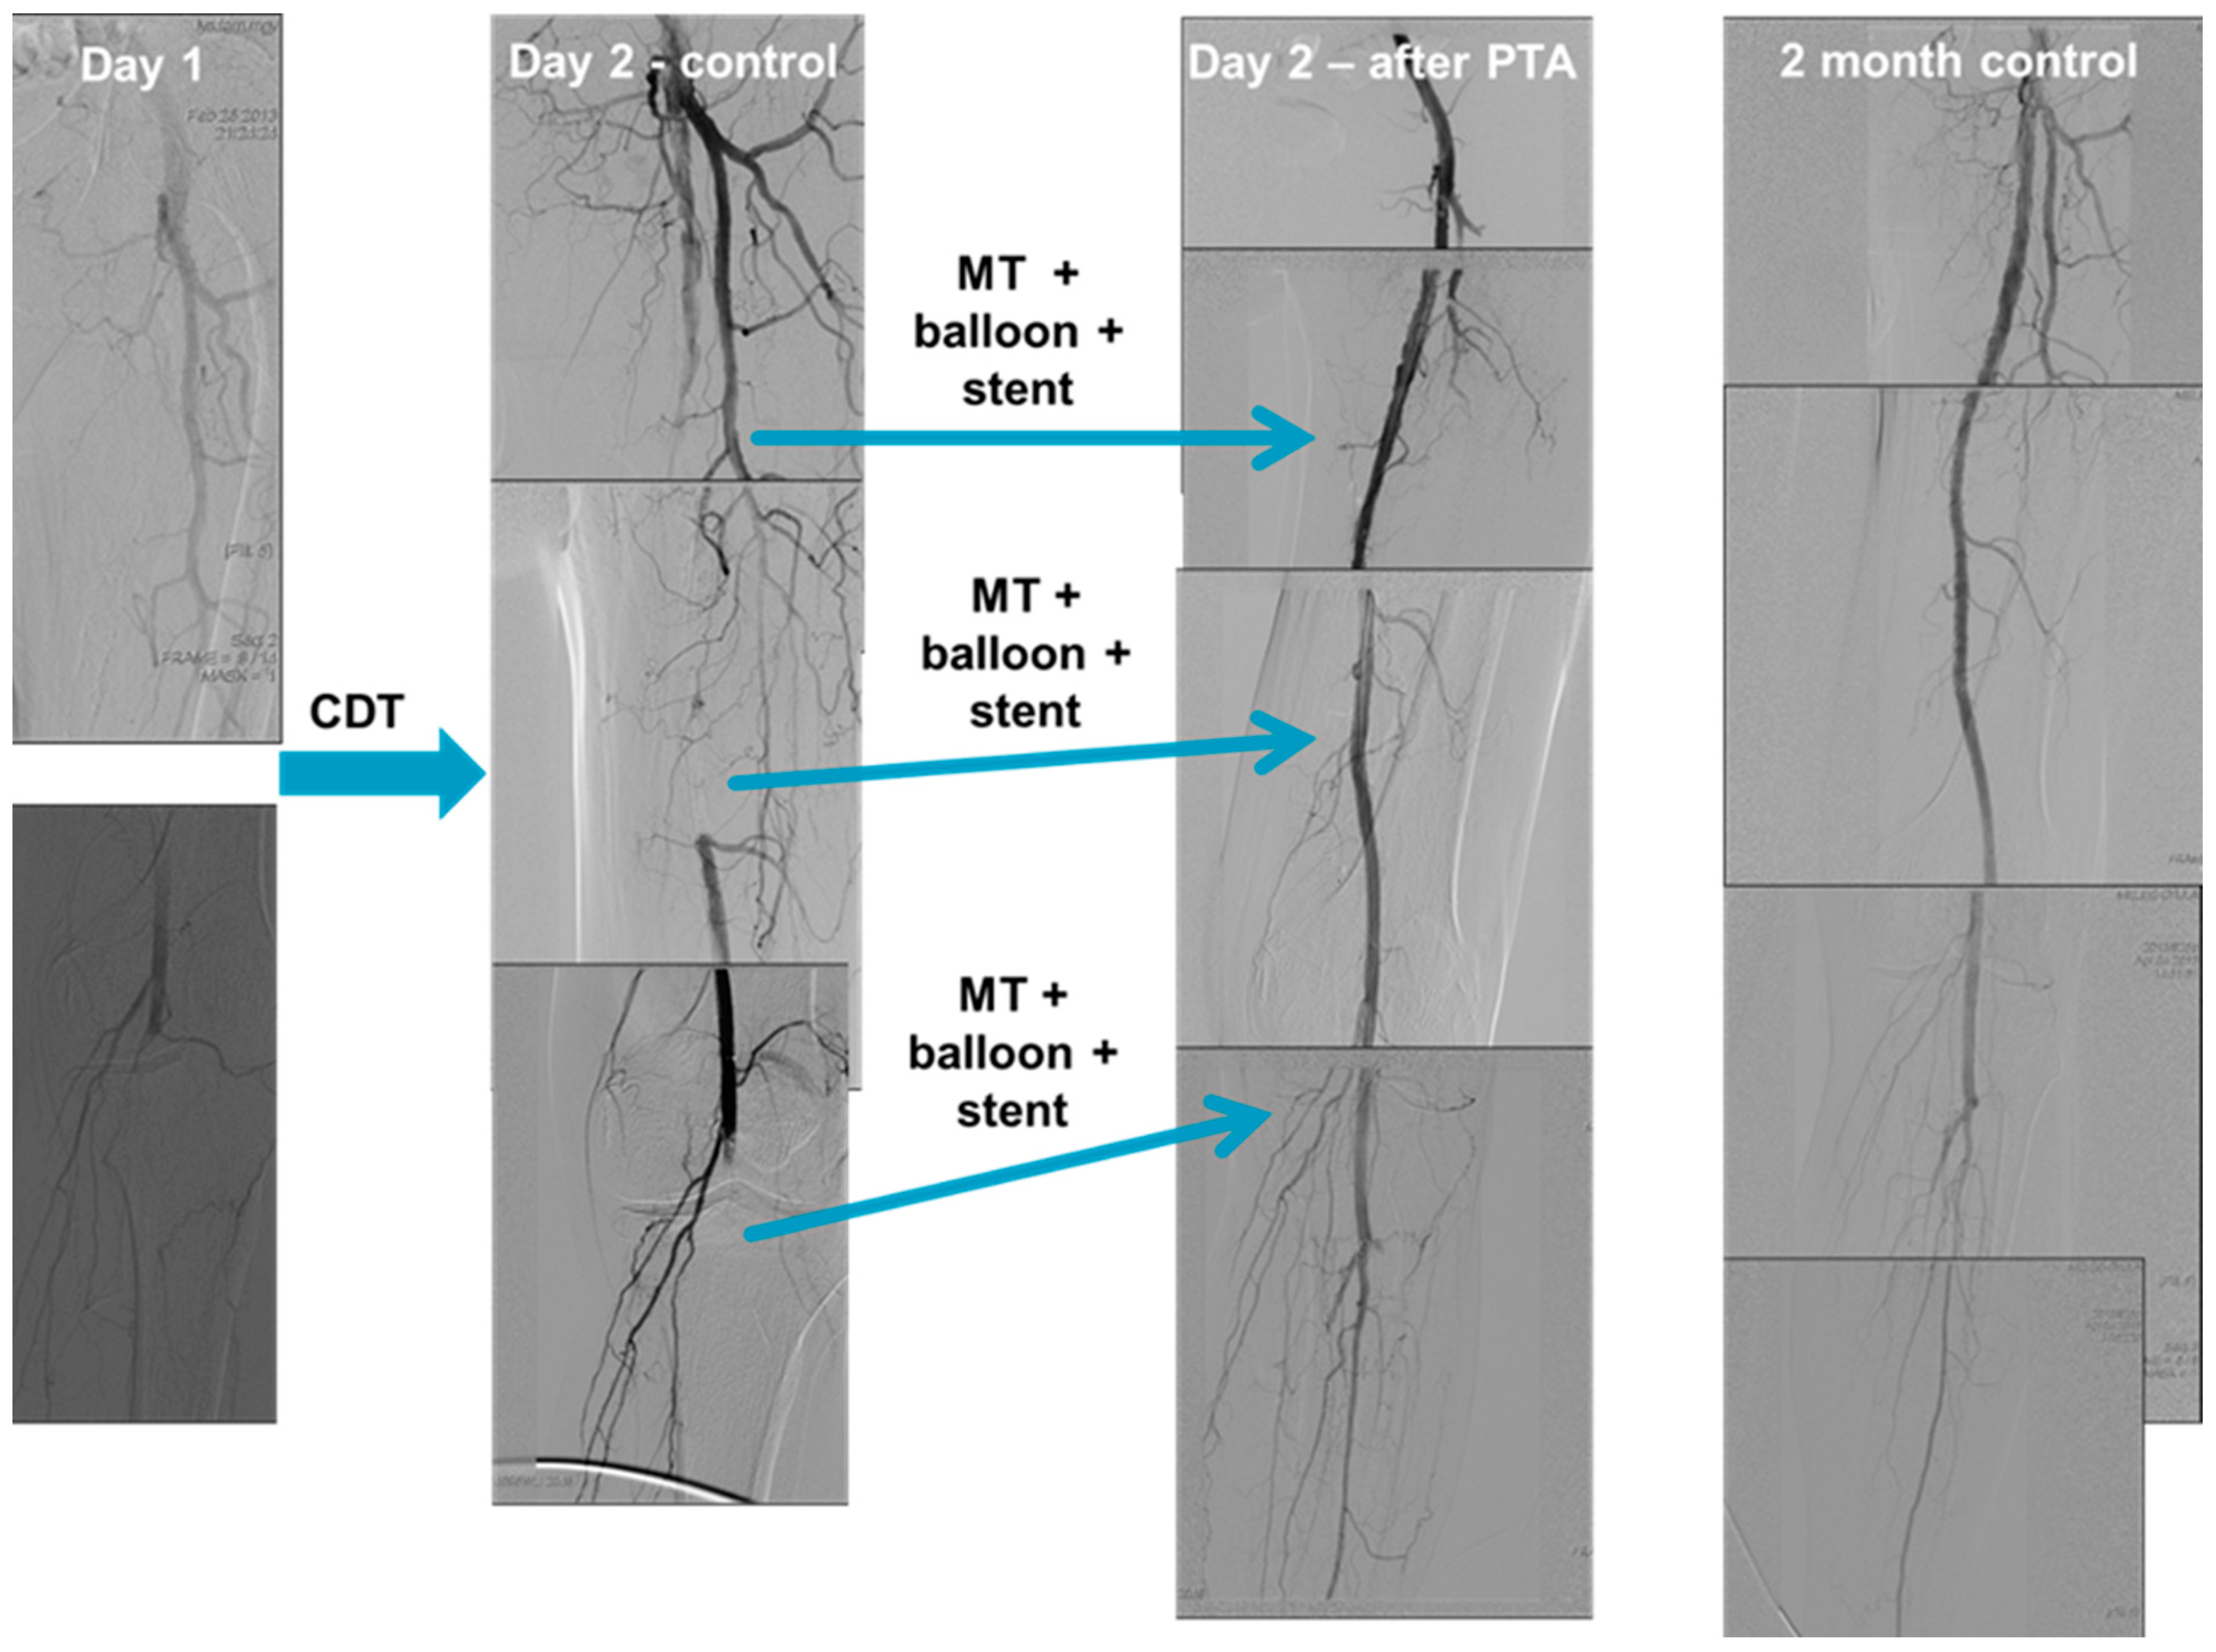

2.4. Catheter Directed Thrombolysis

| CDT | catheter-directed thrombolysis |

| MT | mechanical thrombectomy |

| PTA | percutaneous transluminal angioplasty |